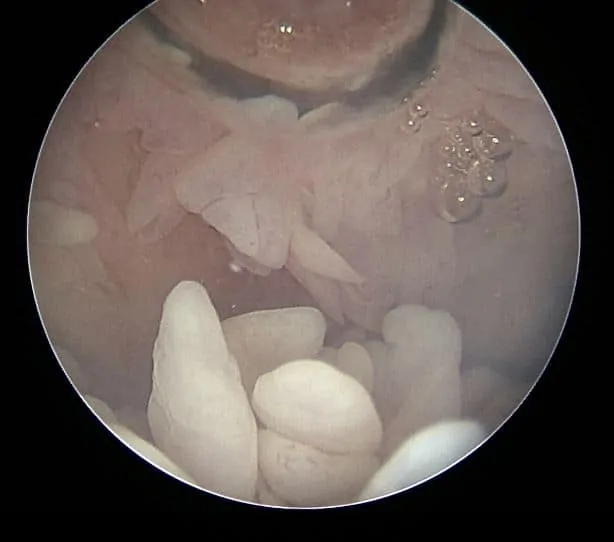

Artroskopske slike sa Dr Dren artroskopa izgled inflamirane sinovije – hronični sinovitis zgloba

Artroskopija kolena omogućuje sposobnom ortopedu u Dr Dren Ortopediji da izvede debridman odnosno uklanjanje nabujale sinovije. Što znači da izvede sinovijektomiju gotovo svih regiona kolena.

Artroskopski snimak iz Dr Dren prakse – uzimanje adekvatnog uzorka izmenjene sinovije i slanje na PH pregled je presudno za dijagnozu i eventualno dalje lečenje posle artroskopije kolena.

Priloženi snimci sa artroskopije kolena. Prikaz kako zaista izgledaju nabujale resice u kolenu